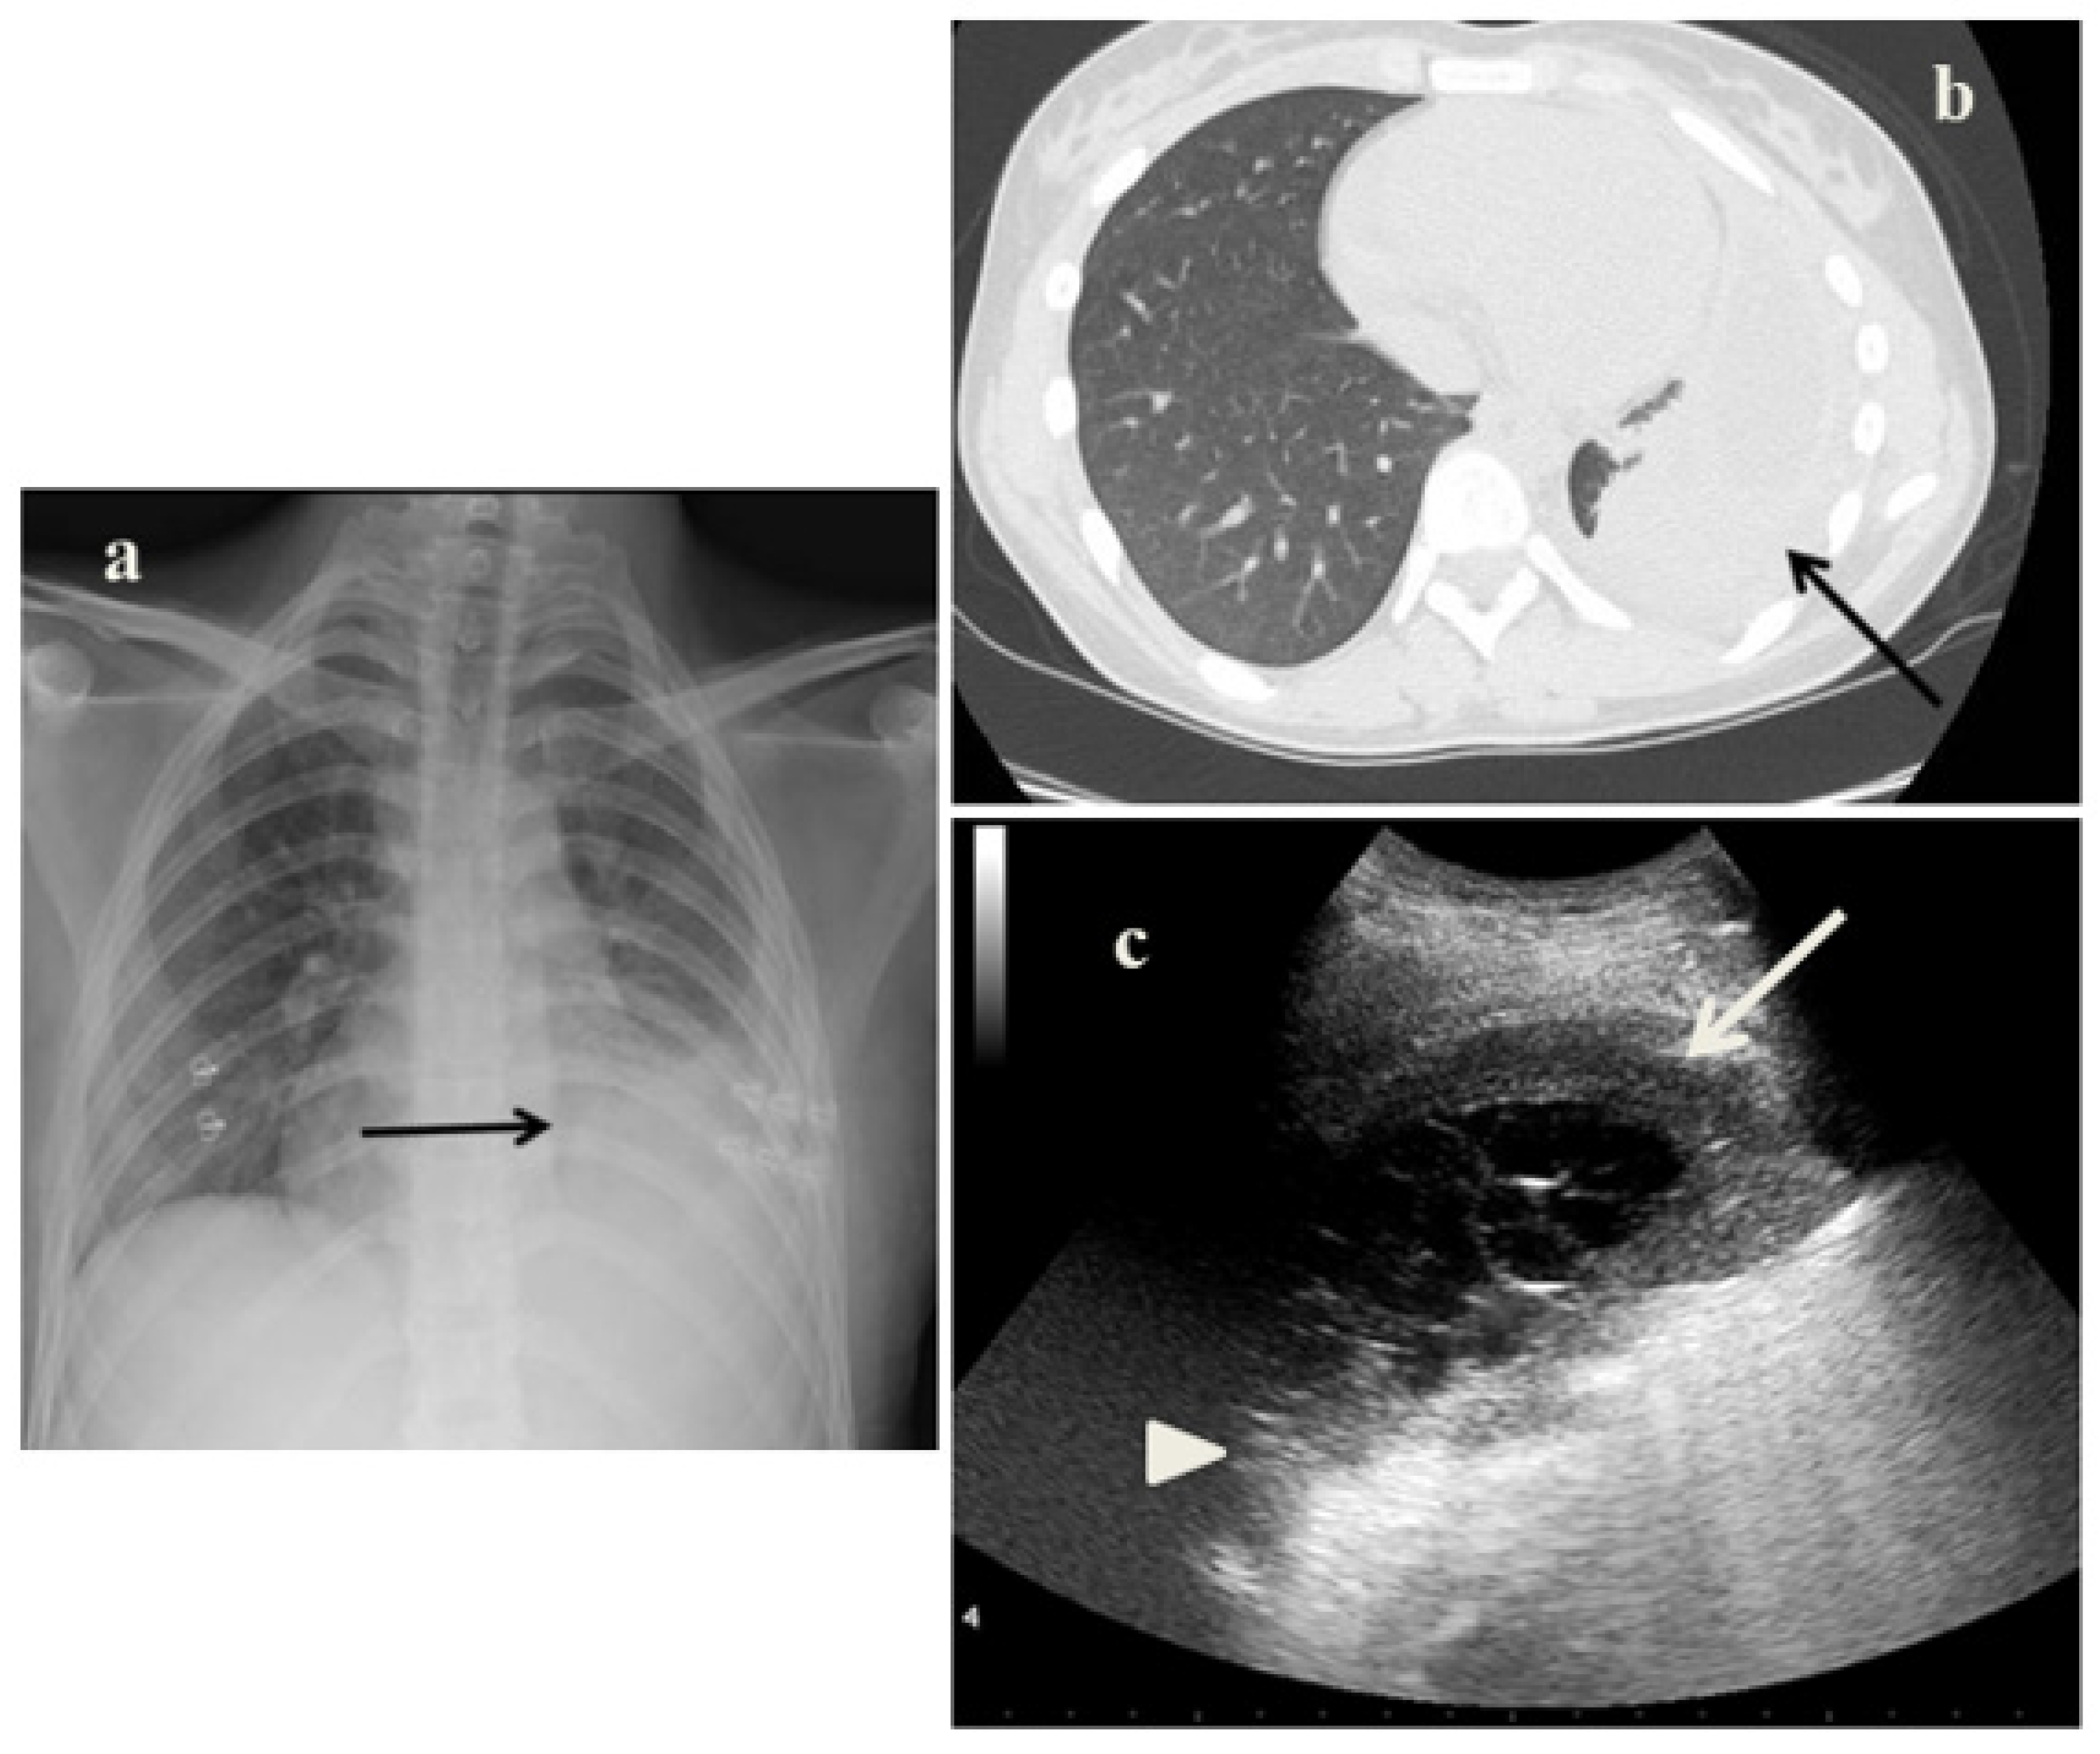

2.2. Case 2

- In the cases 2 and 4, it demonstrated its superiority compared to CXR in characterizing the pleural effusion and consolidation of an atelectatic nature (Figure 2c and Figure 4c); LUS is therefore useful as a non-invasive diagnostic instrumental support to identify and characterize a picture of tuberculous pleuritis.